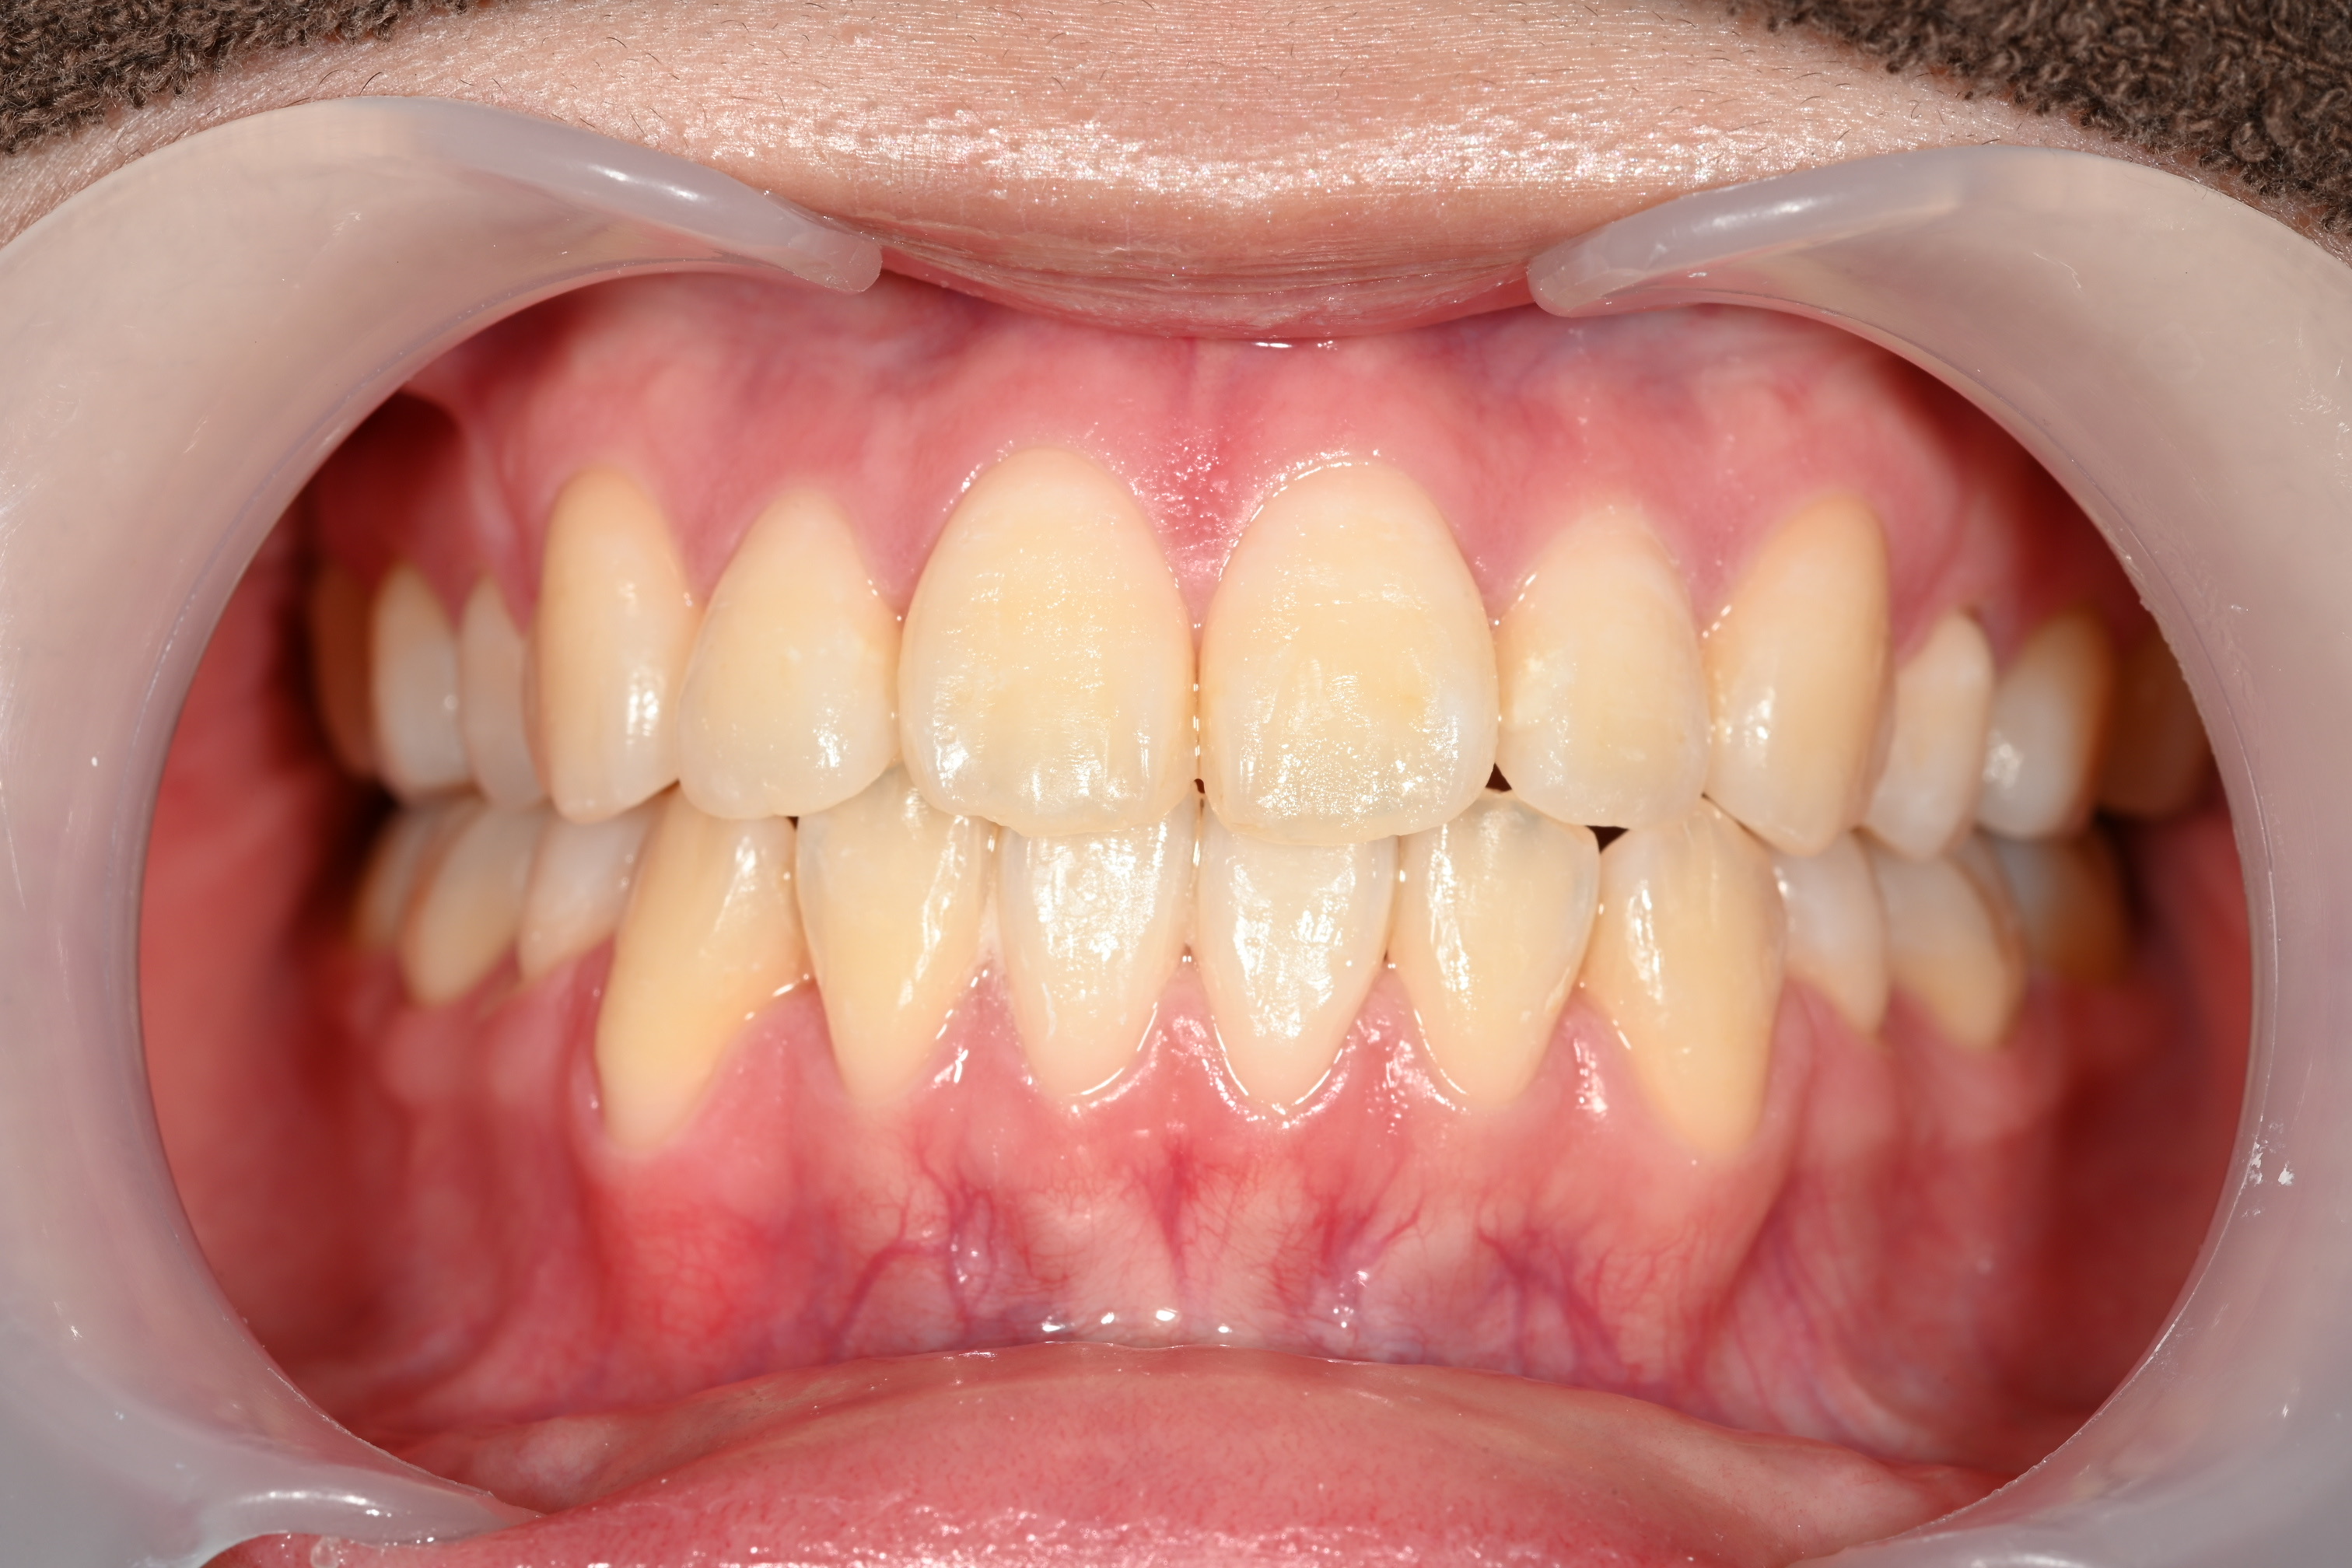

症例⑤

症例5_治療前 症例5_治療後

治療方法 マウスピース矯正

治療期間 2年

治療総額 850,000円

特記事項 抜歯なし